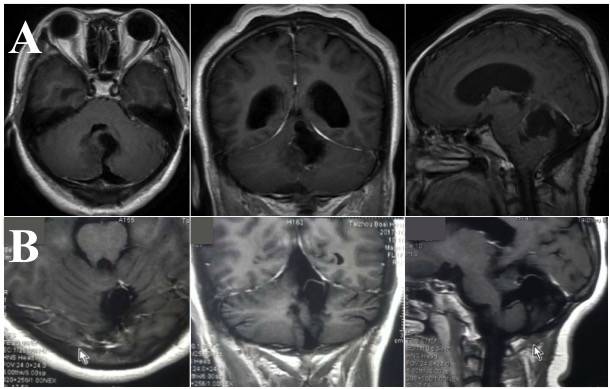

入院后完善头颅增强MRI检查:小脑蚓部囊实性占位,胶质瘤考虑;脑室系统扩张(图1)。

图1. A.增强MRI见小脑蚓部约44mmx48mm囊状影,其内可见分层,囊壁边缘不光整,病灶囊壁局部明显强化;B. 白色箭头处示第四脑室受压变小,另见三脑室及侧脑室扩张。